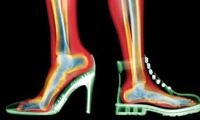

Ayağın 1 tarak kemiği içe doğru kayar bu esnada başparmak da onu. Sivri ve dar ayakkabılar kemik yapısını bozabileceğinden halluks valgus ortaya çıkabilir. Ayakta en sık görülen problemlerden biri halluks valgus denilen halk arasında ayak baş parmak kemik çıkıntısı olarak bilinen bir deformasyondur.